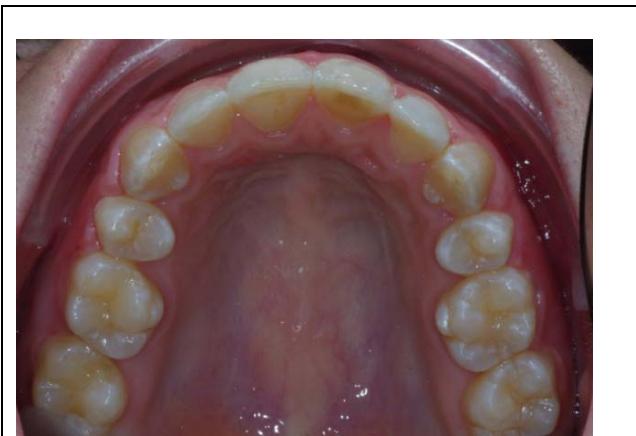

#### Examen endobuccal

L'examen endobuccal montre une supraclusion incisive, une DDM et un sens transversal correct. Dans le sens sagittal, on note une classe Il dentaire.

Examen endobuccal